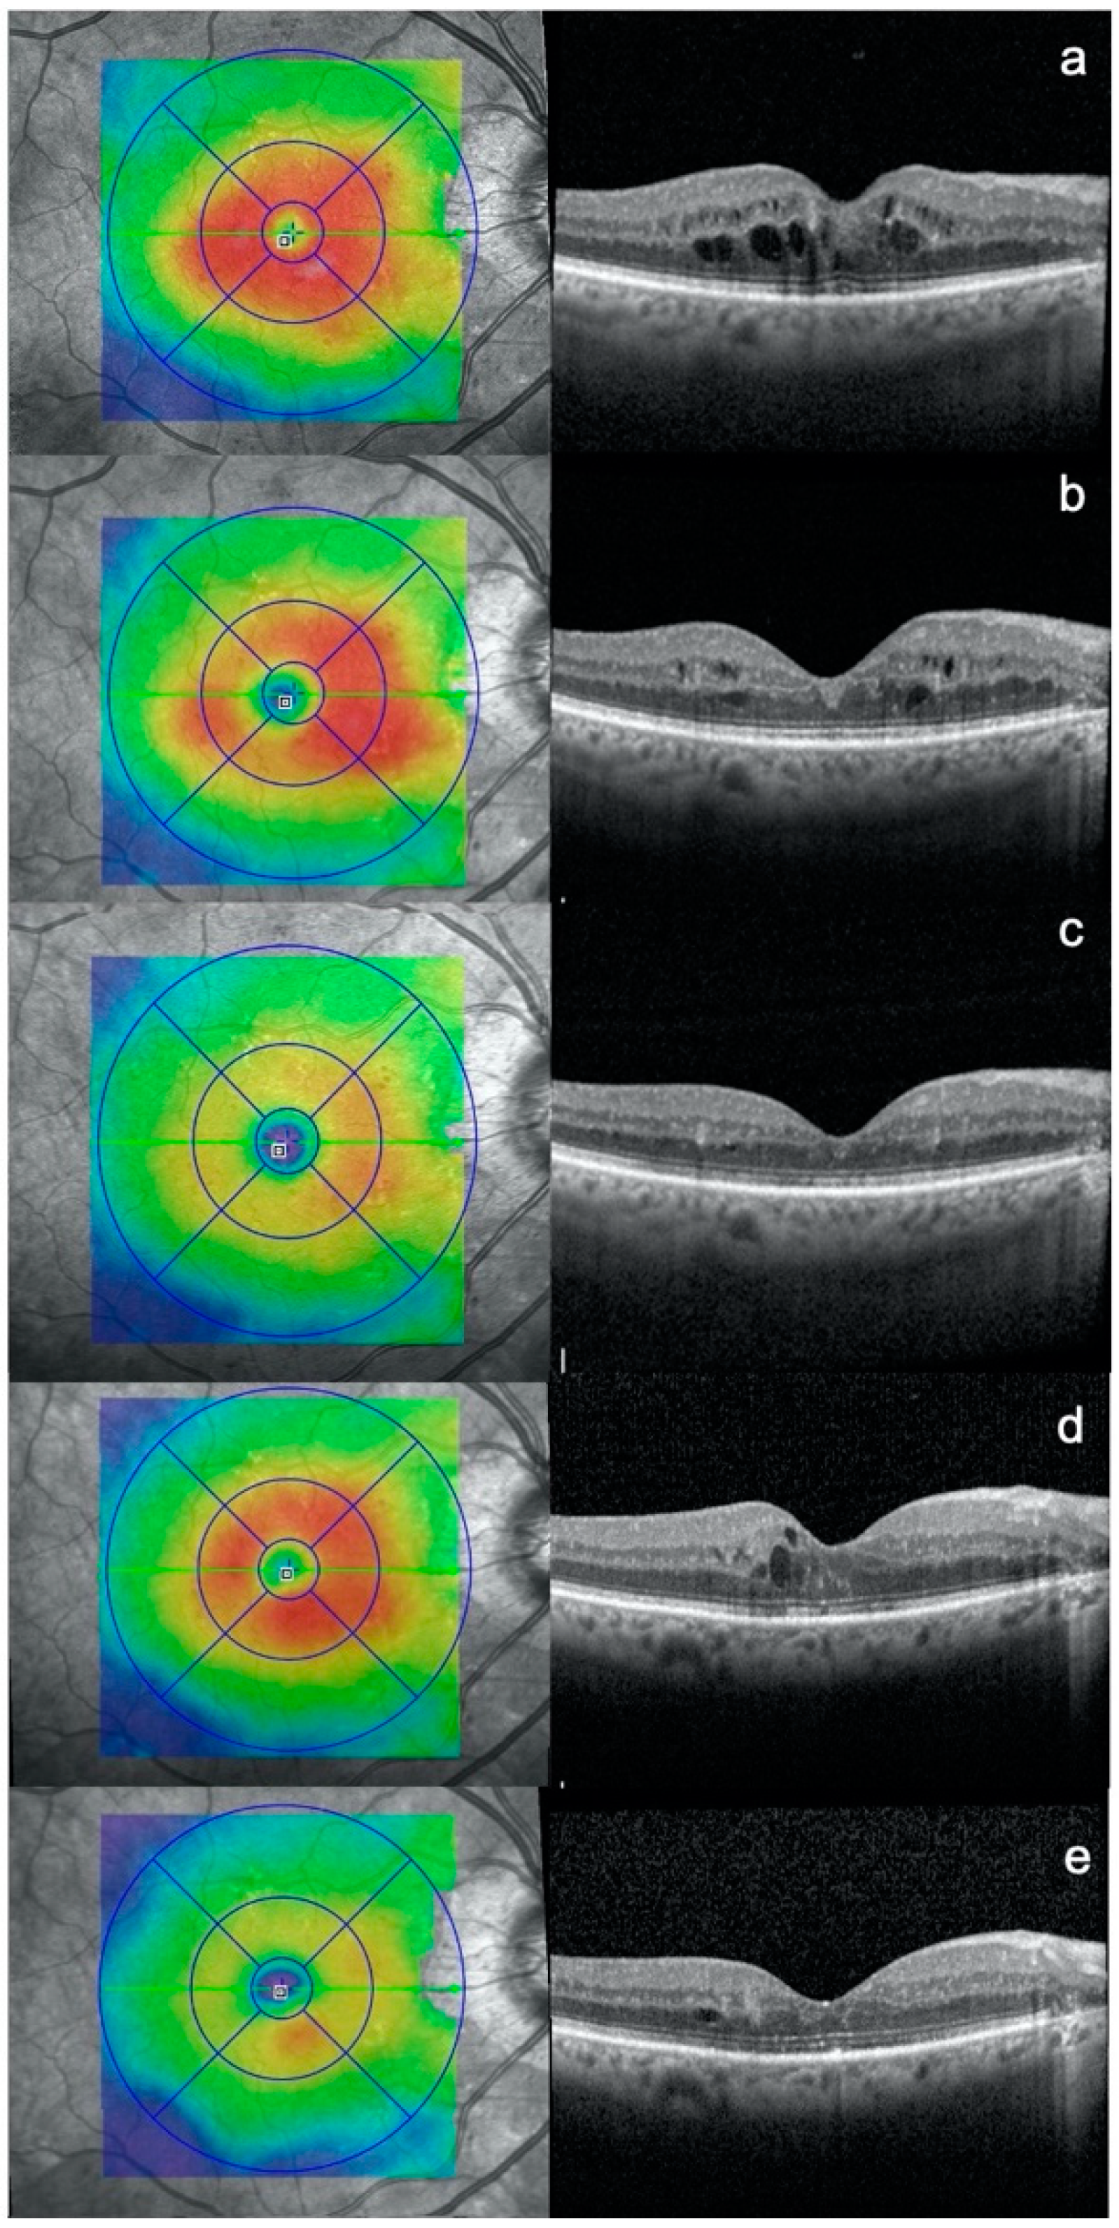

Diabetic Macular Edema Treated with 577-nm Subthreshold Micropulse Laser: A Real-Life, Long-Term Study

3. Results